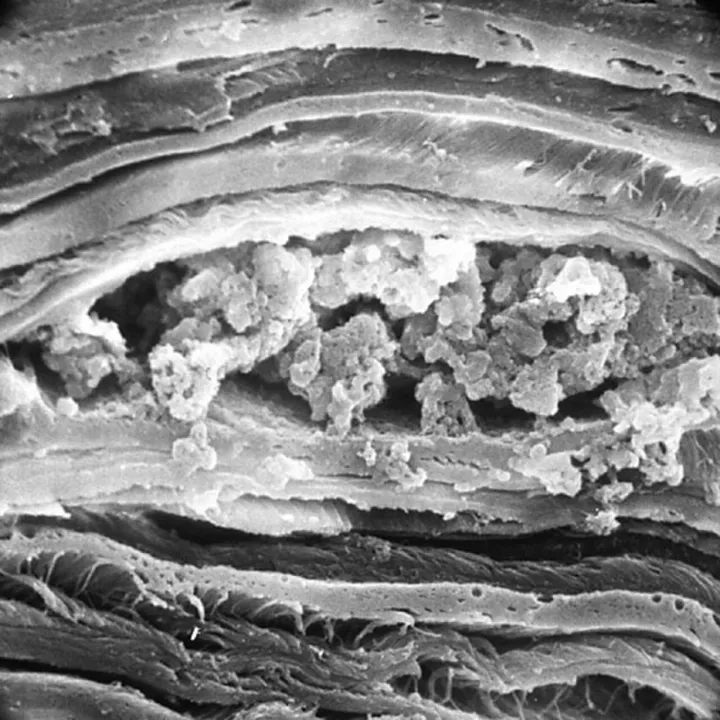

Учёным удалось нарастить кератоциты, которые необходимы для лечения глаз. Учёным удалось нарастить кератоциты, которые необходимы для лечения глаз.© mixyfotos

«Удалось нарастить две популяции клеток — фибробластов и кератоцитов — и оценить инвитро их потенциальный терапевтический эффект. Следующим этапом была создана модель помутнения роговицы на животном глазу. Подопытные организмы мы разделили на четыре группы — одной вводили кератоциты, второй — фибробласты, две были контрольными. Выяснилось, что в моделях с введением клеточной суспензии как кератоцитов, так и фибробластов отчётливо прослеживается тенденция к наиболее быстрому восстановлению прозрачности и толщины роговицы», — пояснила врач-офтальмолог Медицинского научного центра НГУ и МНТК „Микрохирургия глаза“ Кристина Краснер.